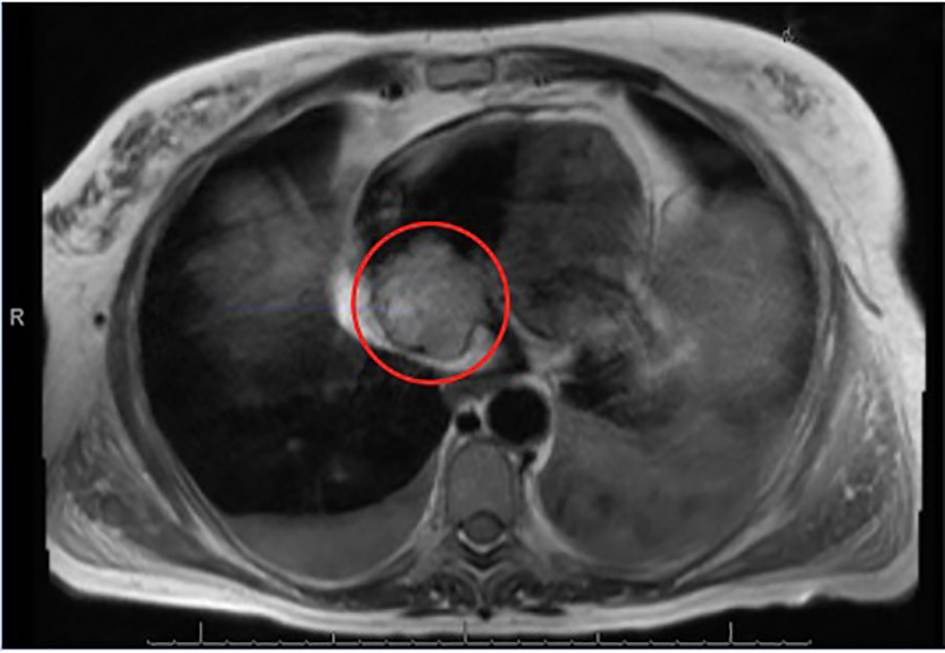

A 69-year-old Caucasian female with a 20-pack-year smoking history and a past history of rectal cancer (stage T3N1M0), treated with neo-adjuvant chemotherapy and radiation, followed by surgical resection with a low anterior resection, ileostomy formation and two subsequent cycles of adjuvant FOLFOX chemotherapy (further chemotherapy had to be aborted secondary to the development of severe neuropathy) presented for further evaluation of worsening dyspnea, fatigue and lower extremity edema 5 years after being lost to oncology follow-up. Her admission labs were significant for mild anemia, thrombocytopenia and acute kidney injury. A CT scan of the chest revealed multiple pulmonary nodules, ascites, a 2.5 cm retroperitoneal lymph node and a mass in the right atrium. A transesophageal echocardiogram revealed a large 4 × 3.5 cm mass in the right atrium (Fig. 1). A cardiac MRI showed the same right atrial mass extending into the tricuspid valve leaflet and the inferior vena cava to the level of the intrahepatic inferior vena cava (Fig. 2). An MRI of the abdomen and pelvis confirmed a heterogeneous, hyper-intense filling defect in the inferior vena cava from the level of the renal veins extending into the right atrium (Figs. 3 and 4). The patient underwent a paracentesis for ascites, which yielded a transudative fluid without malignant cells (WBC 531, ascitic fluid albumin 1.2 g/dL, lactate dehydrogenase 269 U/L (normal 110 - 230 U/L), and serum albumin 2.9 g/dL (normal 3.8 - 5.3 g/dL)). Serum carcinoembryonic antigen (CEA) and carbohydrate antigen 19-9 (CA 19-9) levels were elevated at 42.2 ng/mL (4 ng/mL in 2011) and 49 U/mL, respectively. She underwent a cardiac catheterization with biopsy of the right atrial mass, which revealed carcinoma cells positive for CDX2 and CK20 and negative for CK7 by immunohistochemistry, consistent with metastatic rectal adenocarcinoma. She was started on anticoagulation for the concomitant thrombus and was evaluated by the oncology team who recommended palliative chemotherapy. She declined chemotherapy and ultimately chose home hospice care instead.

![]() Click for large image | Figure 2. A T2-weighted MRI showing the right atrial, non-mobile and heterogeneously hyperintense mass, measuring 4.6 × 4.2 cm. |